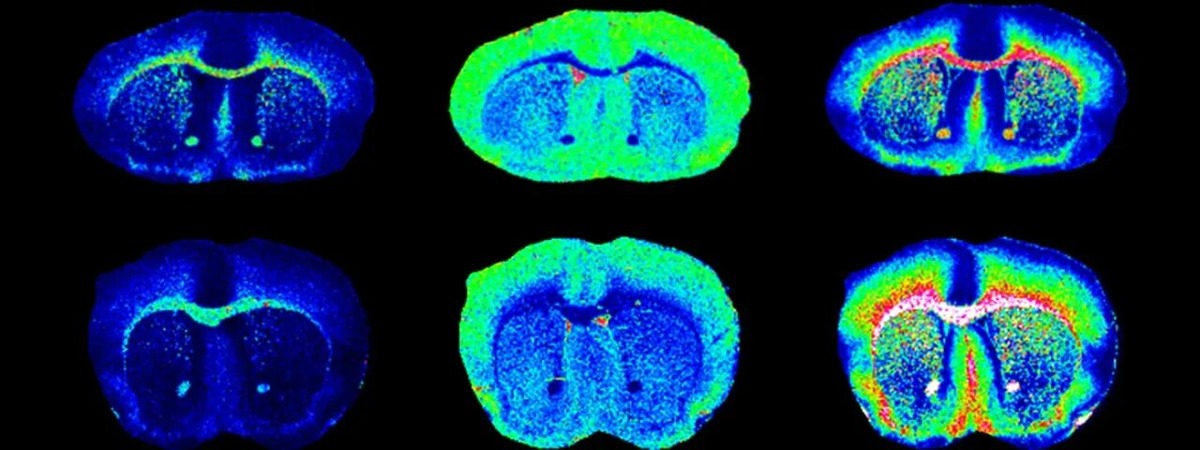

В мае 2025 года исследователи из нескольких ведущих научных институтов США, участвующие в проекте BRAIN Initiative (инициатива NIH — Национального института здравоохранения), представили новый революционный метод доставки генов в мозг. Учёные разработали вирусоподобные носители — молекулярные «грузовики», способные целенаправленно доставлять гены в определённые участки мозга и спинного мозга.

Эти носители основаны на аденоассоциированных вирусах (AAV), которые уже давно используются в генной терапии. Однако до этого момента они имели ограниченные способности проникать сквозь гематоэнцефалический барьер и точно нацеливаться на конкретные нейронные типы. Новые модификации позволяют этому барьеру обходиться, а терапевтический генетический материал — доставляться в заданную область без значительных побочных эффектов.

1. Инженерные вирусы: Учёные модифицировали AAV, улучшив их способность проходить через защитный барьер мозга.

2. Нацеленность: Каждый «грузовик» программируется для доставки в строго определённый участок — например, гиппокамп, ствол мозга или спинной мозг.

3. Безопасность: В отличие от классических вирусных векторов, новые носители демонстрируют повышенную биосовместимость и минимальное воспаление в тканях.